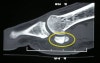

CT : 종자골 골절(Sesamoid fracture, Sesamoiditis)

MRI에서는 골절이 있으면 골수부종 소견이 나타납니다(족장판(plantar plate), 종자뼈사이 인대, 굴근건을 평가하는데에도 MRI가 도움이 됩니다).